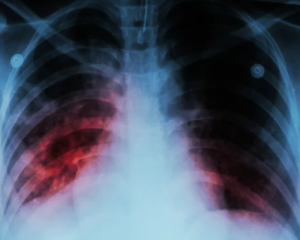

Всемирная организация здравоохранения предупреждает, что туберкулез продолжает оставаться одной из самых опасных инфекций в мире, хотя эту болезнь можно как предотвратить, так и вылечить.

По обновленным данным, в 2024 году туберкулез унес жизни 1,2 млн человек, а количество инфицированных достигло 10,7 млн. человек.

Глава ВОЗ Тедрос Адханом Гебрейесус подчеркнул, что, несмотря на "заметный прогресс" в диагностике, лечении и разработке новых решений, уменьшение заболеваемости на 2% и смертности на 3% по сравнению с 2023 годом нельзя назвать окончательной победой.

По его словам, "тот факт, что туберкулез продолжает уносить более миллиона жизней ежегодно, несмотря на то, что его можно предотвратить и вылечить, просто возмутительный".

Он подчеркнул необходимость ускорения движения к глобальной цели - полной ликвидации туберкулеза до 2030 года.

Падение показателей заболеваемости связывают с возобновлением работы систем здравоохранения после сбоев, вызванных пандемией Covid-19.

Самым серьезным барьером в борьбе с болезнью остается нехватка средств. Глобальное финансирование противотуберкулезных программ не увеличивалось с 2020 года. В 2024-м на профилактику, выявление и лечение туберкулеза выделили лишь $5,9 млрд - около четверти необходимых $22 млрд, которые планируют привлечь к 2027 году.

ВОЗ предостерегает, что ожидаемое сокращение донорского финансирования с 2025 года может привести к росту числа смертей до 2 млн и увеличению заболеваемости до 10 млн. в период с 2025 по 2035 год.

Для преодоления туберкулеза нужны ускоренные действия, прежде всего, в странах, наиболее страдающих этой болезнью.

В 2024 году 87% всех случаев приходилось на 30 государств, причем 67% - на восемь из них: Индию (25%), Индонезию (10%), Филиппины (6,8%), Китай (6,5%), Пакистан (6,3%), Нигерию (4,8%), ДР Конго, ДР Конго.

С 2000 года благодаря лечению туберкулеза удалось сохранить жизнь 83 млн человек.